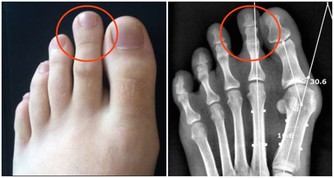

提取物之一姬松茸:能增強骨髓造血功能,使外周血的血紅蛋白,血小板及白細胞明顯升高,增強對進行放療和化療的患者的敏感性和耐受性,減少毒副作用,還能增強人體免疫力